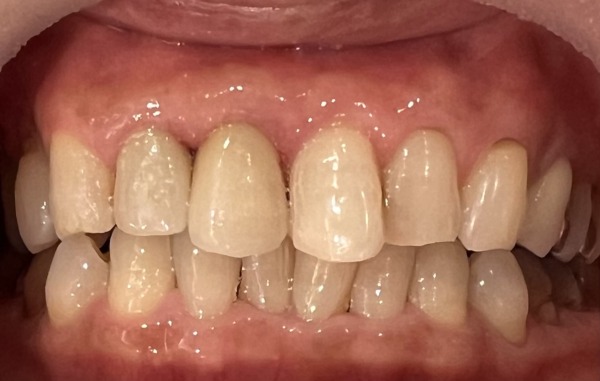

7日目 2本のセラミックの被せ物を装着しました。

セラミックの形は、唇や頬とのバランスを見ながら作成する必要があります。歯科技工士に口腔内の状態をより正確に伝えるため、仮歯を付けた状態で型取りをします。また、歯の色を撮影し、ご自身の色に合わせて作成しました。

治療後の様子

患者様は日頃から歯周病の進行を防ぐため、歯間ブラシやフロスを使用していましたが、なかなか細かいところまでは届いておらず、被せ物の内部で虫歯が再発していたことにショックを受けていました。検診では、お口の中を細かく検査することで、虫歯を早期発見でき、定期検診の重要さを改めて感じたとおっしゃっていました。